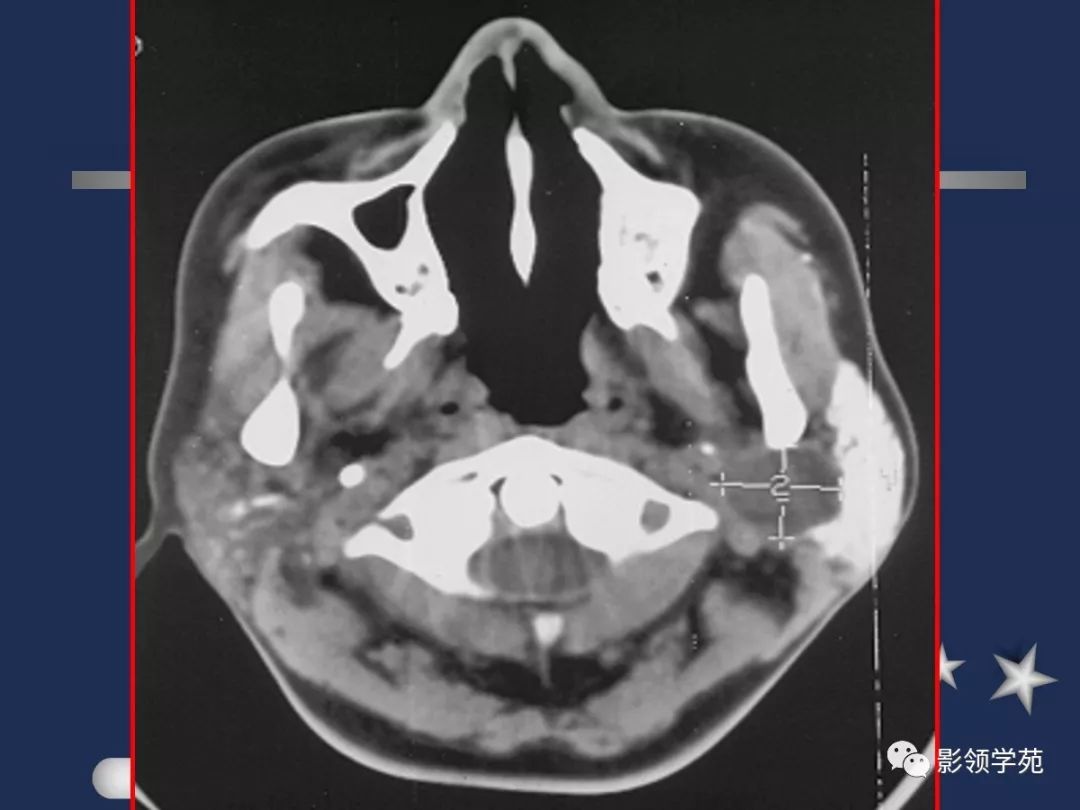

- 位于下颌骨后,胸锁乳突肌前,上致颅底,位于乳突尖和颞颌关节之间,下至下颌角,是茎突前咽旁间隙重要器官

- 腮腺是脂肪性腺体,CT呈低密度

- 腮腺内血管显示清楚